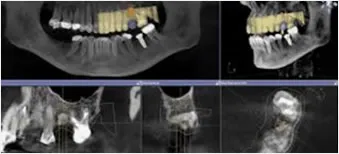

Cone Bean Dental 3-D CT

Ciudadela Dental Implants has the Highest State of the Art Facility for Dental Implants in Puerto Rico

Digital X Rays